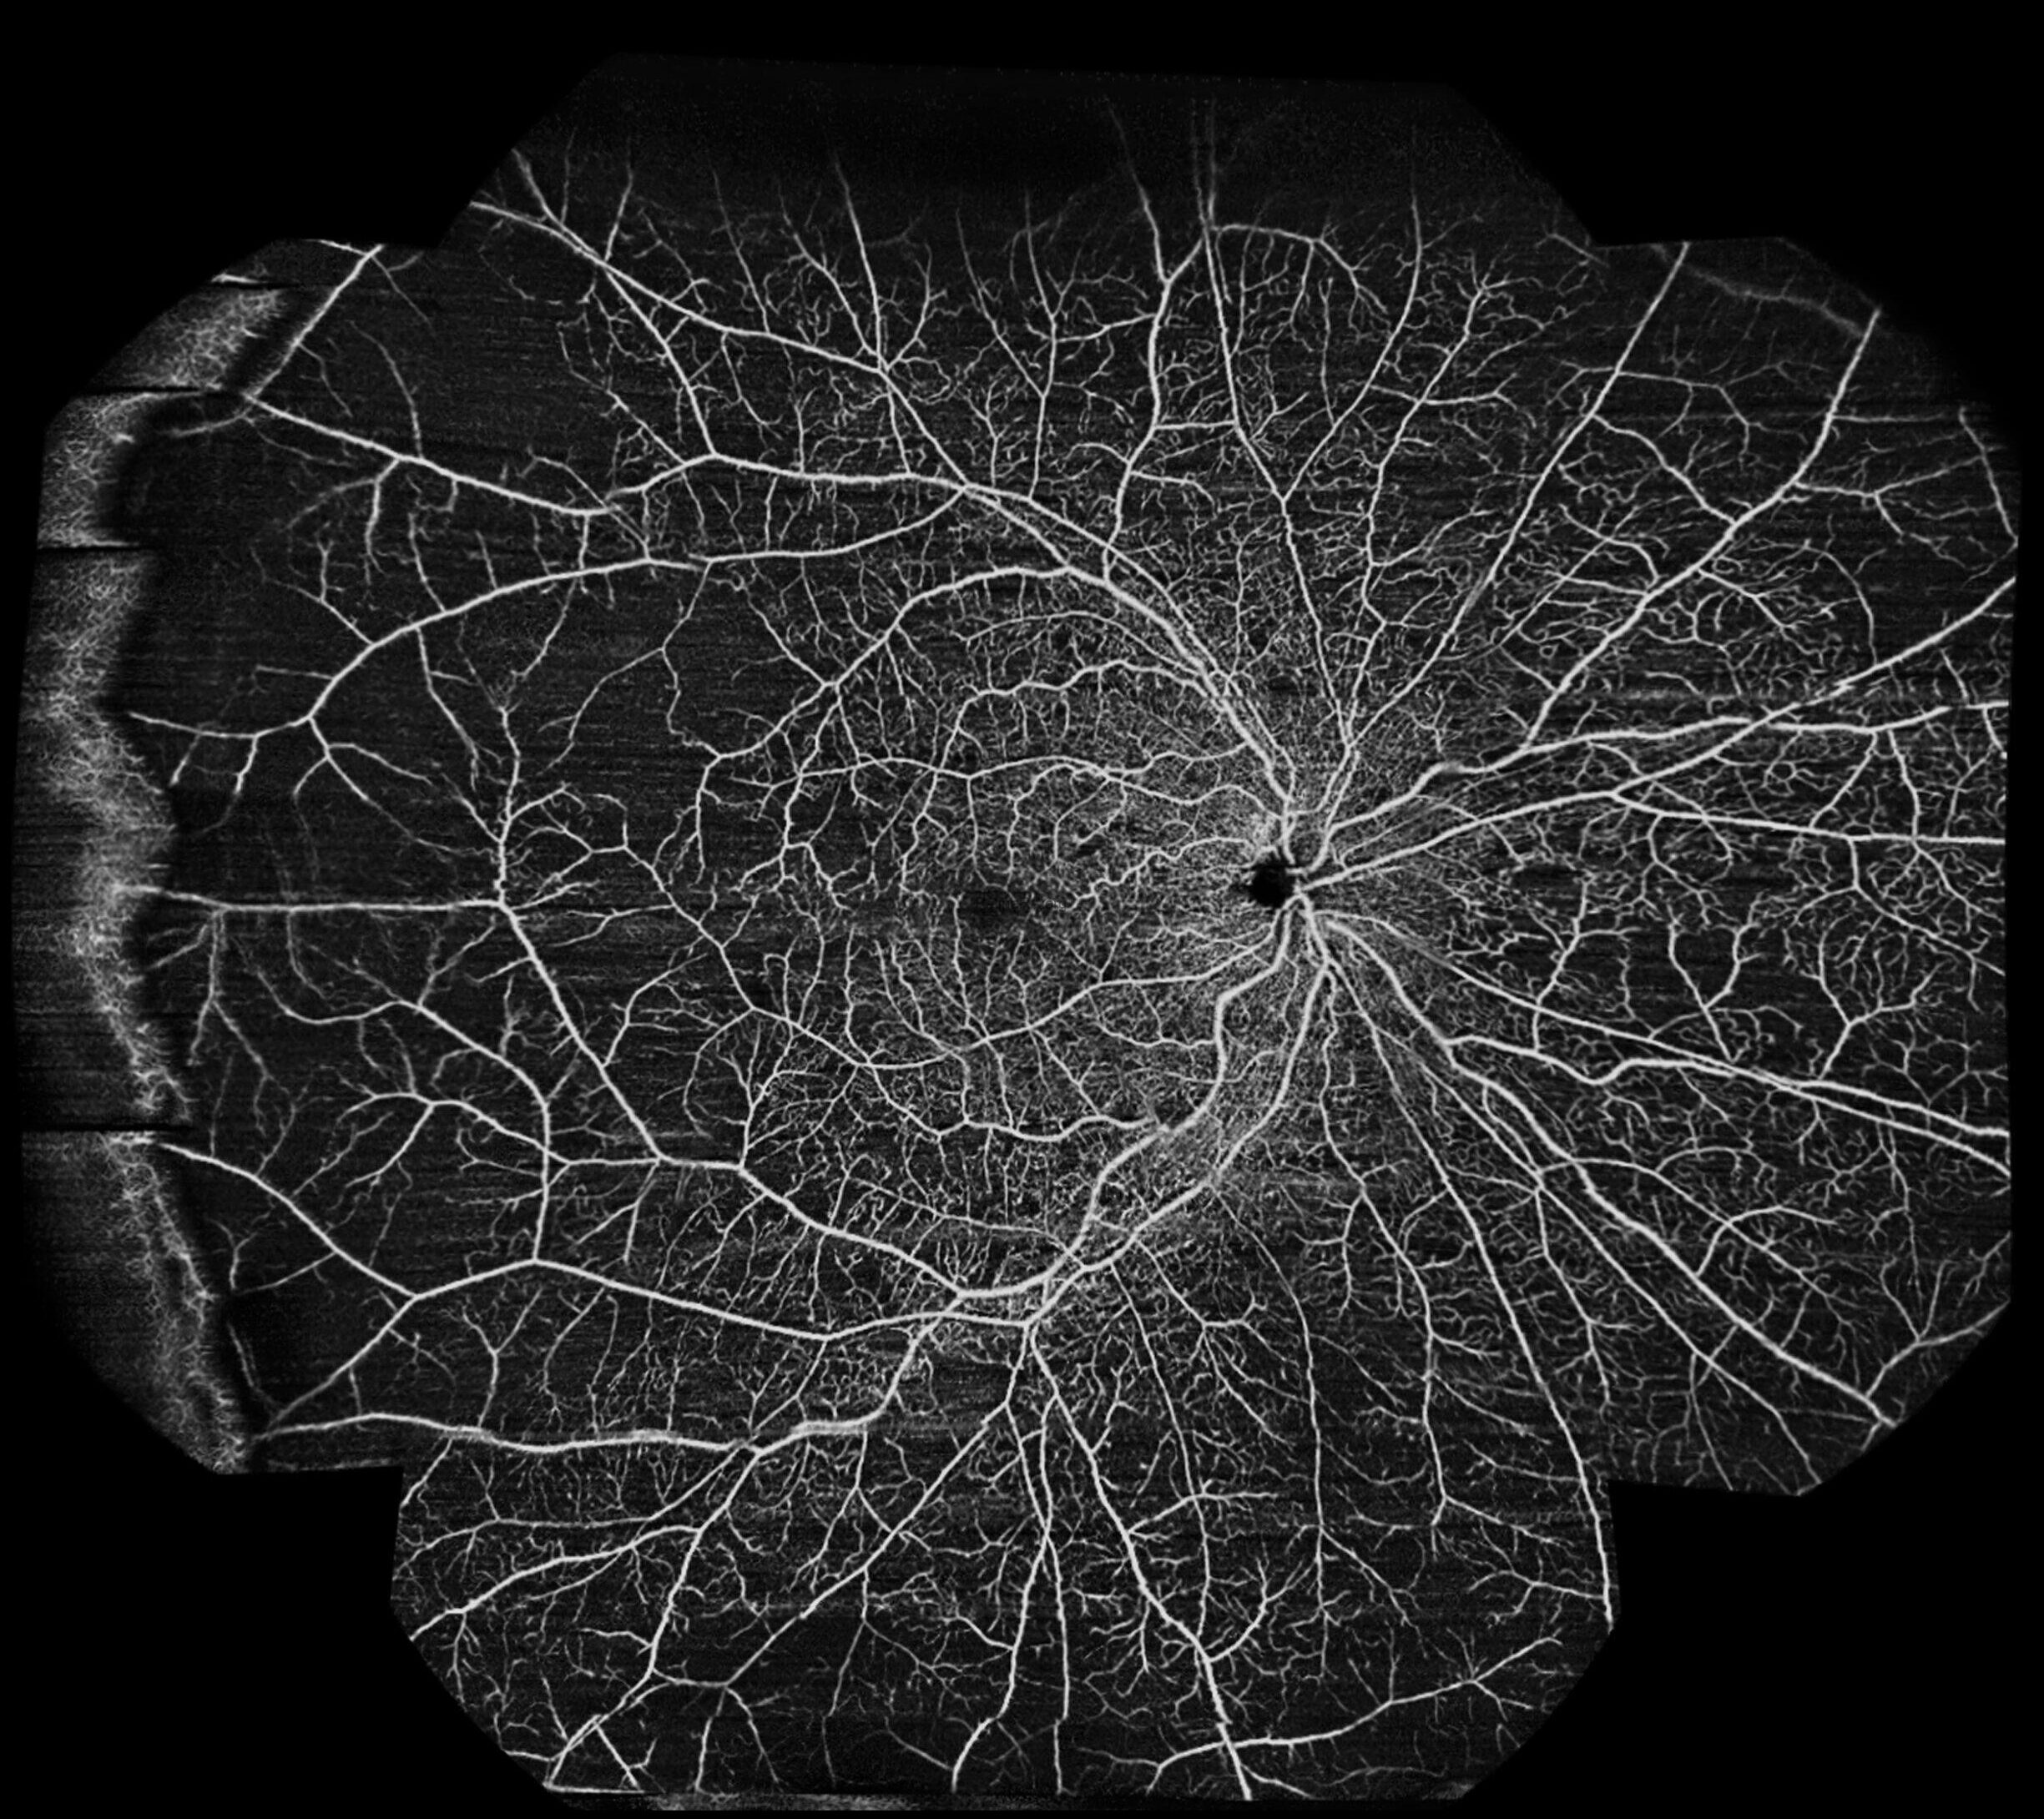

The ultra-widefield OCTA image provides an extended view of the retinal vasculature beyond the posterior pole. In the post-treatment scan, the superficial vascular plexus (top image) demonstrates improved perfusion centrally, although extensive areas of capillary nonperfusion are still evident in the midperiphery and periphery. The deep plexus (second one) reveals more pronounced dropout, with diffuse hypoperfused zones reflecting irreversible ischemic damage. Overall, the ultra-widefield OCTA highlights the persistent peripheral ischemia in spite of treatment, underlining the value of widefield imaging in assessing the full extent of vascular compromise in central retinal vein occlusion.